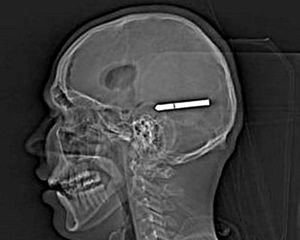

X ray

Metal rod found inside the skull